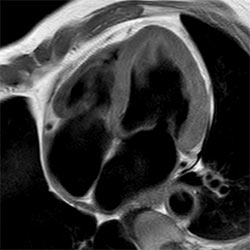

Pelvis